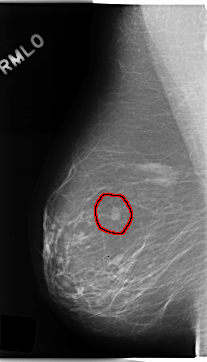

C_0192_1.RIGHT_MLO

RIGHT_MLO LINES 4704 PIXELS_PER_LINE 2680 BITS_PER_PIXEL 12 RESOLUTION 50 OVERLAY

FILE: C_0192_1.RIGHT_MLO.OVERLAY

TOTAL_ABNORMALITIES 1

ABNORMALITY 1

LESION_TYPE MASS SHAPE OVAL MARGINS SPICULATED

ASSESSMENT 5

SUBTLETY 5

PATHOLOGY MALIGNANT

TOTAL_OUTLINES 1

BOUNDARY